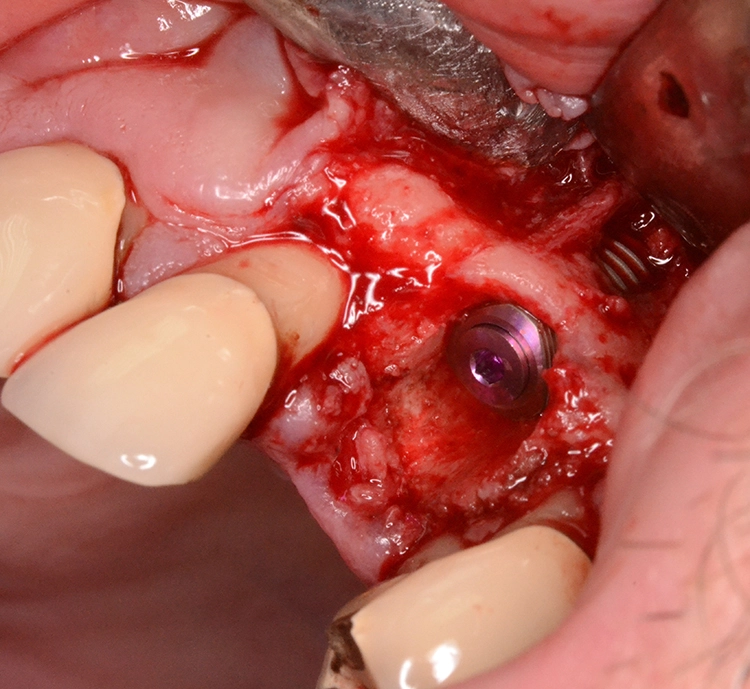

Im präoperativ angefertigten DVT (Abb. 3b und c) zeigte sich um die Wurzelspitze ein chronisches Entzündungsgeschehen, welches die vestibuläre Lamelle im apikalen Wurzelbereich des Zahnes 23 komplett aufgelöst hat. Da jedoch der Bereich direkt apikal von 23 nicht vom Geschehen betroffen war, fiel die Entscheidung zur Sofortimplantation auch, da der Patient blutverdünnende Medikamente einnehmen musste, welche durch Kombination von Extraktion und Implantation nur einmal abgesetzt werden mussten. In diesem Fall war aufgrund des Knochendefektes die Bildung eines Volllappens mit Entlastung unumgänglich.

Dr. Opitz

Anschließend wurde der Knochendefekt mit kortikospongiösem Knochengranulat aufgefüllt und mit einer langsam resorbierenden Kollagenmembran versorgt (Abb. 3e und f). Das OP-Gebiet musste im Anschluss aufgrund der Augmentation vollständig gedeckt werden (Abb. 3g).